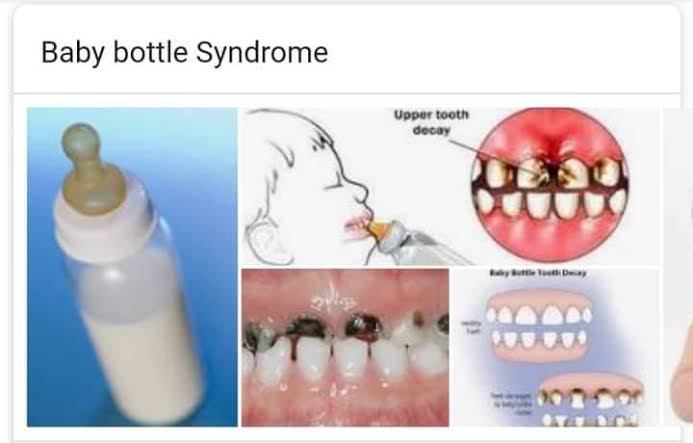

புதிதாக பிறந்த குழந்தைகளுக்கு உடல் பராமரிப்பு மட்டுமின்றி வாய் சுகாதாரமும் மிக அவசியம் . அதற்க்கான வழிமுறைகளை பார்ப்போம்

ஈறுகளை சுத்தம் செய்யுங்கள்உணவளித்த பிறகு, உங்கள் குழந்தையின் ஈறுகளை சுத்தமான ஈரமான துணி அல்லது காஸ்பேட் மூலம் மெதுவாக துடைக்கவும். இது பாக்டீரியாக்களை அகற்றவும் , குவிவதை தடுக்கவும்உதவுகின்றது

பால் பாட்டில் பற்சொத்தை தவிர்க்கவும்பால், பார்முலா, பழச்சாறு (ஜூஸ்) அல்லது எந்த சர்க்கரை திரவத்தையும் கொண்ட பாட்டிலை வாயில் வைத்து குழந்தைகளை தூங்கவிடாதீர்கள். இது பற்சிதைவிற்கு வழிவகுக்கும். இதற்கு நர்சிங் பாட்டில் கேரிஸ் (Nursing bottle caries) என்று பெயர்.

ஆரம்பகால பல் பராமரிப்பு

முதல் பல் தோன்றியவுடன், பொதுவாக ஆறு மாதங்களுக்குள், குழந்தைகளுக்காக பிரத்தேயமாக வடிவைமைக்கப்பட்ட சிறிய மென்மையான பிரிசில்ஸ் (Bristles) கொண்ட பல் துலக்குதலை பயன்படுத்த தொடங்குங்கள். தண்ணீர் அல்லது ஃவுளூரைடு பற்பசையைக் கொண்டு மெதுவாக துலக்குங்கள்.

பல் மருத்துவரை அணுகவும்உங்கள் குழந்தை பிறந்தது முதல், பல் தோன்றிய ஆறு மாதங்களுக்குள், முதல் பல் மருத்துவ சந்திப்பை திட்டமிடுங்கள். இதன் மூலம் பல் மருத்துவர் உங்களுக்கு தேவையான வழிகாட்டுதலை வழங்குவார்.

ஆரோக்கியமான உணவுப் பழக்கம்

தாய் பாலூட்டுதல் தாடை வளர்ச்சிக்கு மிக முக்கியமான ஓன்று. மிகச் சரியான பால் பாட்டிலை தேர்ந்தெடுக்க வேண்டும். அதிக சர்க்கரை உணவுகளை தவிர்க்கவும்.

குழந்தைகளுக்கான பாத்திரங்கள்

குழந்தைகளுக்கு உபயோகிக்கும் பாத்திரங்கள்,Pacifier (ரப்பர் நிப்பிள்) ஆகியவை வேறு எவரும் பயன்படுத்தக்கூடாது. இதன் மூலம் பாக்டீரியாக்கள் குழந்தையின் வாயிற்குள் செல்வதை தடுக்கலாம். குழந்தையின் பாத்திரங்களை தனியாக சுடுநீரில் சுத்தப்படுத்தி உபயோகிக்கவும். குழந்தை பருவத்தில் பல் பாதுகாப்பு, அவர்கள் ஆரோக்கியமா இருக்கவும், நன்கு உண்ணவும், நன்கு பேசவும் மிக உதவியாக இருக்கும்.